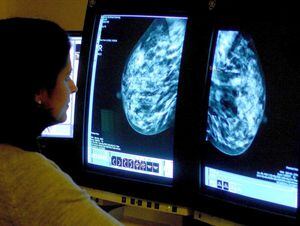

Breast screening IT error affected about 2,000 women in Shropshire

About 2,000 women in Shropshire were affected by the NHS breast cancer screening failure, it has been revealed.

Health Secretary Jeremy Hunt told the House of Commons last month that hundreds of thousands of women had not been sent invitations for the scans since 2009 because of a national computer error.

Nationally, the error led to 450,000 people missing out on their final routine breast cancer screening.

Women aged between 50 and 70 are supposed to be invited for a mammogram every three years.